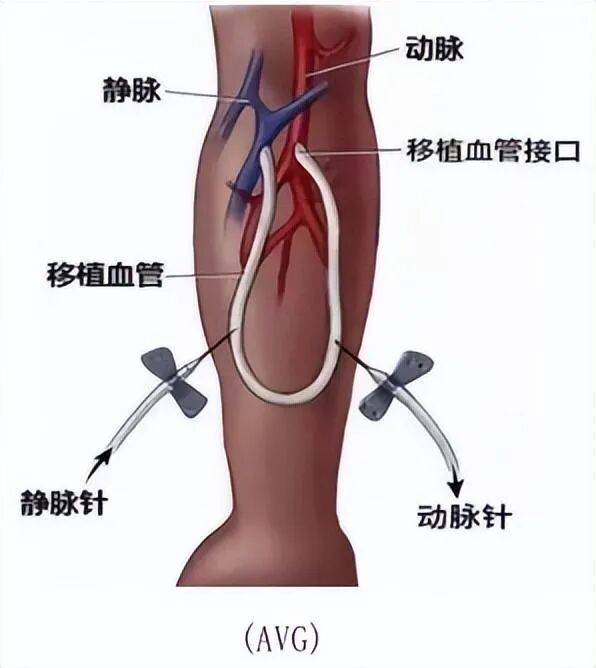

眾所周知,良好的血管通路,是血液透析的基本條件論文。但並不是所有尿毒症患者都有條件建立自體動靜脈內瘻。很多患者(尤其是老年人、糖尿病患者、高血壓患者、肥胖者)的自身血管可能因為硬化、纖細、閉塞或因反覆穿刺而受損,無法滿足透析所需的血流量或無法進行手術。人工血管移植提供了新的穿刺部位,延續了患者的透析生命。為自身血管條件差、無法建立自體動靜脈內瘻的尿毒症患者,提供一條穩定可靠的“生命線”。但是,人工血管後期的併發症目前在國內外均研究較少。在過去十年中,具有多層結構的早期穿刺動靜脈移植物問世,可在植入後 24–72 小時內進行穿刺,以滿足緊急透析需求。然而,這種特殊結構使其易發生夾層這一獨特併發症。

圖2:透析人工血管移植(AVG)示意圖